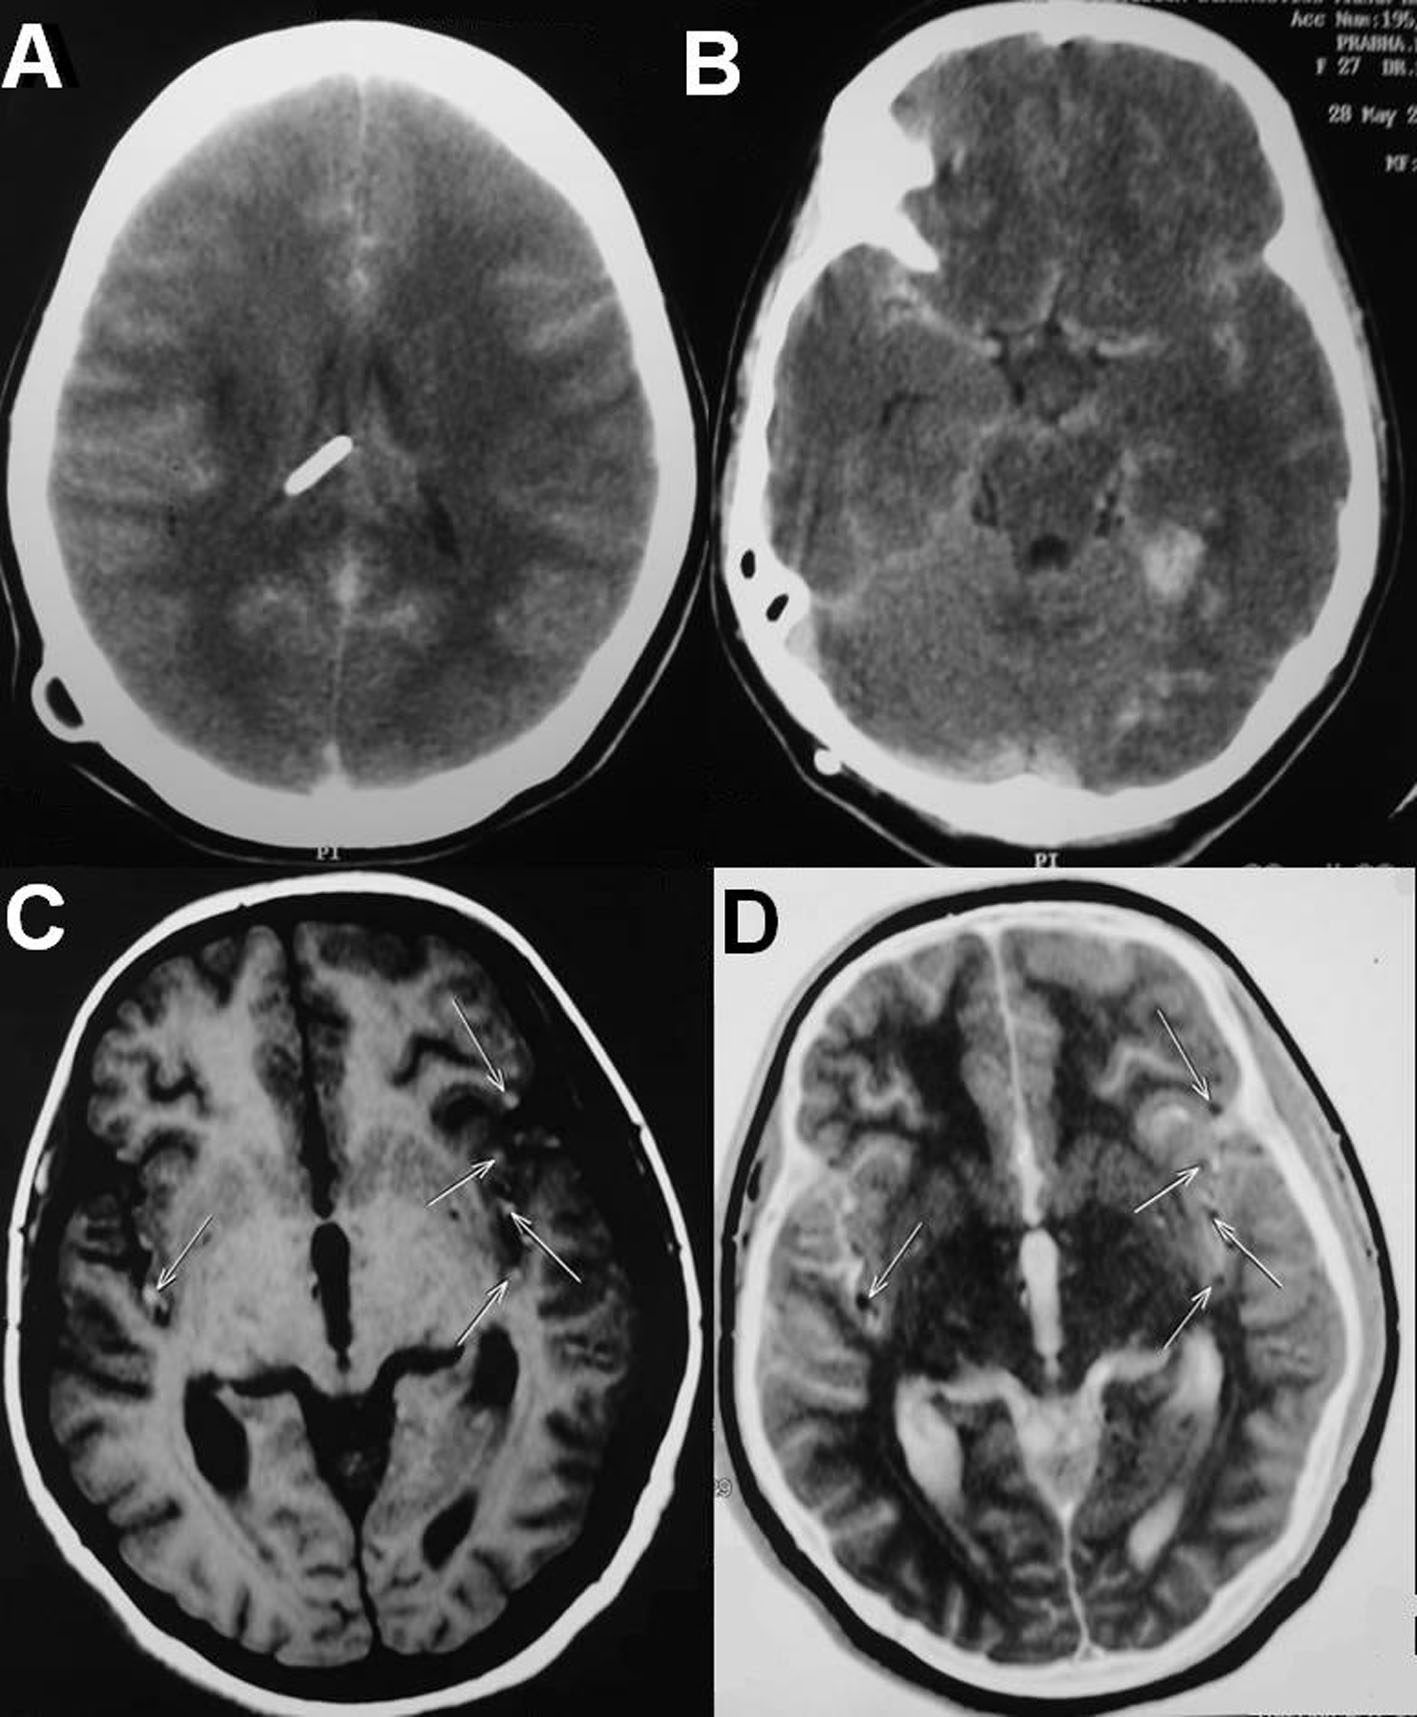

She underwent D4 and D8 laminectomies and total excision of the lesions at two levels. The lesions were intradural extramedullary dirty black in color, soft in consistency, easily separable from the spinal cord and were attached to the overlying dura. HPE and immunohistochemistry were consistent with metastatic deposits of malignant melanoma. Postoperatively she improved in her paresis by one MRC grade. On second postoperative day she started having frequent episodes of irrelevant speech and the next day she became drowsy with respiratory distress. She was intubated and ventilated. Repeat CT scan of the brain showed multiple small tumour emboli with evidence of right temporal bleed and diffuse cerebral edema (Fig. 4A, B). The tumor emboli were clearly made out in the MRI of the brain (Fig. 4C, D). She was given aggressive antiedema measures in spite of which she expired on the fourth postoperative day as a result of malignant cerebral edema.

![]() Click for large image | Figure 4. (A, B) Repeat CT scans of the brain showing multiple small tumor emboli with evidence of right temporal bleed and diffuse cerebral edema. (C, D) MRI of the brain showing the tumor emboli on both the hemispheres in middle cerebral artery territory. |